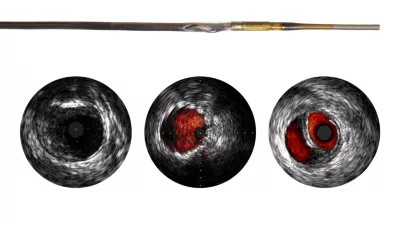

Visions PV 0.018” y PV 0.035”

Catéter digital de IVUS